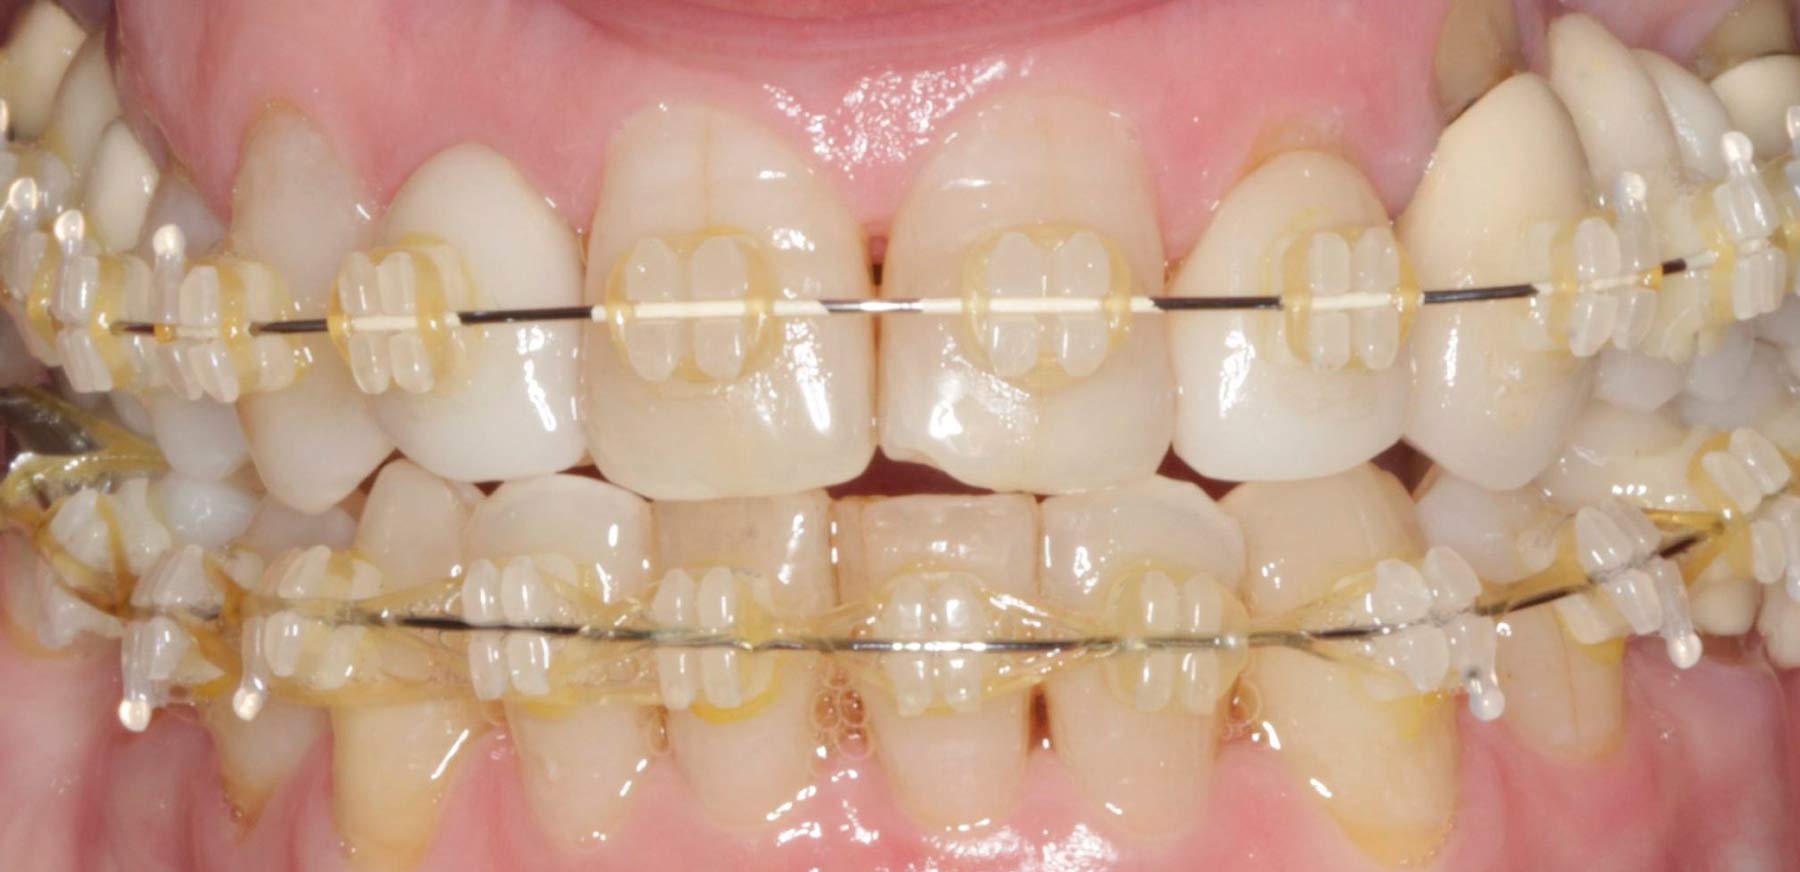

Lo primero era evaluar su estado dental y establecer un pronóstico a largo plazo. Para ello, se realizaron radiografías, registros fotográficos, impresiones y arco facial.

Esta paciente quería cambiar sus viejas prótesis de metal-cerámica, con más de 25 años, por algo más estético. Presentaba recesiones, zonas de atrofia, problemas en la arcada dental y estéticamente, una excesiva exposición gingival, márgenes irregulares y diferencias de color entre la restauraciones y sus dientes originales.

Empezamos primero por un tratamiento de ortodoncia para alinear y nivelar la mordida. Después, esta paciente pasó por periodoncia para resolver la recesión gingival. En cuanto a la nueva prótesis, se decidió realizar un nuevo puente, ya que sus dientes contaban con hueso suficiente para ello y en buen estado. Para finalizar, las diferencias de forma y color, se corrigieron con carillas dentales.